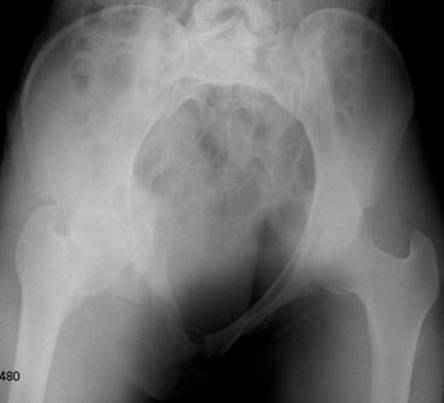

Уважаемые коллеги!

Спасибо за полезные советы! По inlet и outlet обнаружили перелом крестцас той-же стороны. Сегодня прооперировали реконструктивной пластиной с перекрытием симфиза, крестец, увы, фиксировать было нечем - оставили так (тем более, что грубой дислокации там нет). Рентгенограммы выложу позже.

Серия до- и послеоперационных снимков этой пациентки. Хотя бы post factum обсудить. Не знаю, что можно сделать с задними отделами стержневым аппаратом, но три крепких парня открытым путем с помощью "волшебных" слов еле-еле смогли отрепонировать - сзади все было очень ригидно!